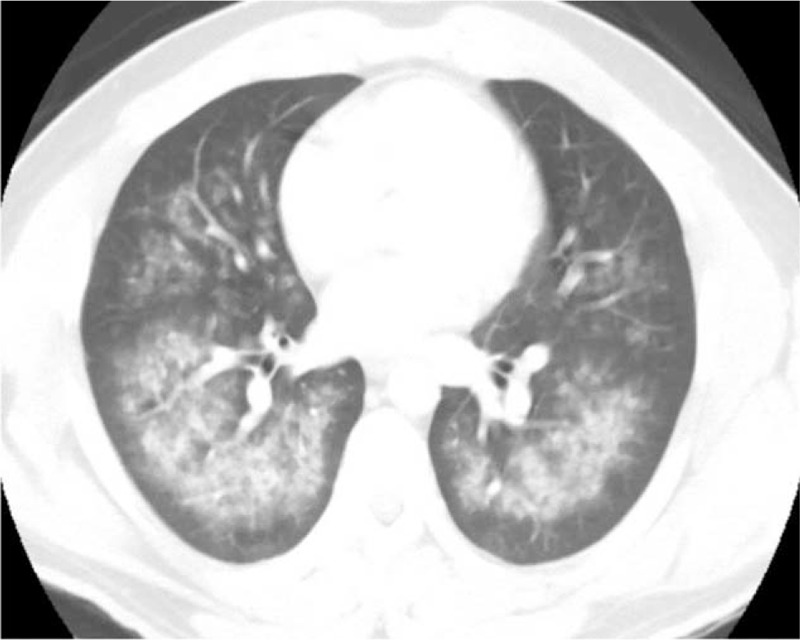

Chest radiograph (Figure 1A) showed increased interstitial markings and chest computed tomography (CT) scans (Figures 2 and 3) showed diffuse ground-glass opacities. An echocardiogram indicated a normal ejection fraction of 66% with no valvular abnormalities. A bronchoscopy with bronchoalveolar lavage (BAL) was initially bloody, but subsequently became clear (Figure 4). BAL cell counts showed leukocytes at 120 cells/mm3, with 98% neutrophils, and red blood cells at 28,250 × 106 cells/mm3. A transbronchial biopsy revealed chronic inflammation. The hemoglobin was 15.8 g/dl, coagulation profile was normal, vasculitis work up consisting of antinuclear antibody, rheumatoid factor, anti-DNA antibody, and antiglomerular basement membrane antibody was negative. The patient’s beta natriuretic peptide was 13 pg/ml and his urine toxicology was positive for cannabinoids.